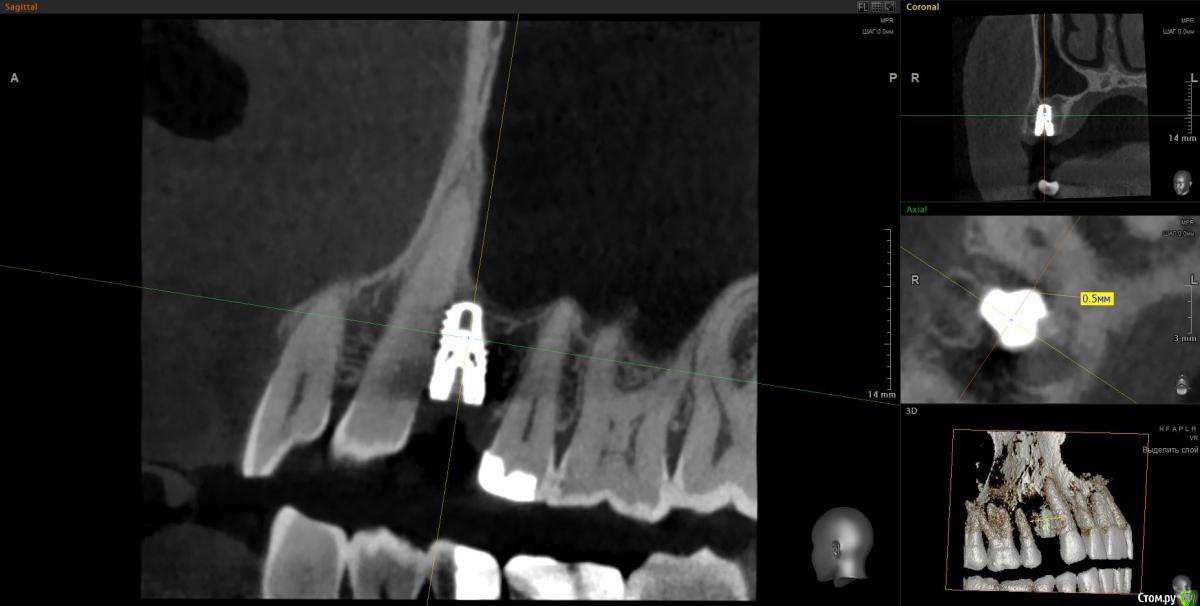

Doctor Vlad Опубликовано 14 апреля, 2020 Поделиться Опубликовано 14 апреля, 2020 Вчера одномоментно. кт только сегодня. Жалоб нет. Хотя там и сст с неба. конечно клык не сверленый, но близость напрягает. Съехал он при установке. Поленился снимок делать после установки, ушил лунку с трансплантатом, во рту норм выглядел. А потом на рг не очень) контроль кт Оставить? убрать недели через 3? Ссылка на комментарий

It'sGeorgy Опубликовано 14 апреля, 2020 Поделиться Опубликовано 14 апреля, 2020 Вчера одномоментно. кт только сегодня. Жалоб нет. Хотя там и сст с неба. конечно клык не сверленый, но близость напрягает. Съехал он при установке. Поленился снимок делать после установки, ушил лунку с трансплантатом, во рту норм выглядел. А потом на рг не очень) контроль кт Оставить? убрать недели через 3?Если есть уверенность, что в следующий раз получится поставить лучше и успешно провести ЗСЛ - я бы убрал. Какие показания к удалению? Я бы оставил, не вижу проблемы 0.7 мм рисково между зубов и винтом, на мой взгляд оставлять. Ну и по глубине тоже, ябдокрутил. Ссылка на комментарий

Doctor Vlad Опубликовано 14 апреля, 2020 Поделиться Опубликовано 14 апреля, 2020 Если есть уверенность, что в следующий раз получится поставить лучше и успешно провести ЗСЛ - я бы убрал. 0.7 мм рисково между зубов и винтом, на мой взгляд оставлять. Ну и по глубине тоже, ябдокрутил. было такое в практике, чем опасно? Ссылка на комментарий

Doctor Vlad Опубликовано 14 апреля, 2020 Поделиться Опубликовано 14 апреля, 2020 Имплант с полированной шейкой, по замерам мм на 2 ниже вестибулярной пластинки Ссылка на комментарий

Doctor Vlad Опубликовано 16 апреля, 2020 Поделиться Опубликовано 16 апреля, 2020 Объясните-в чем опасность? Не понимаю...С зубом проблем не будет, имплант без компрессии там лежит и не травмирует. Но в плане протезирования и долгосрочной перспективы хочется видеть его ровней и на равном удалении от зубов. следующий имплант будет уже. ось его на центр выходит между 13 и 15 но 1 мм от платформы до 13 зуба маловато. Опыта в таких случаях нет. В нижних резцах тоже бывает меньше мм 1 остается и все норм. Хотелось бы поглубже. Сейчас он на мм 2 заглублен от кортикалки и мм 3.5 по десне. но пройдет ремоделировка и будет меньше, а может и нет. Если бы я его протезировал может быть оставил бы посмотреть. Ссылка на комментарий